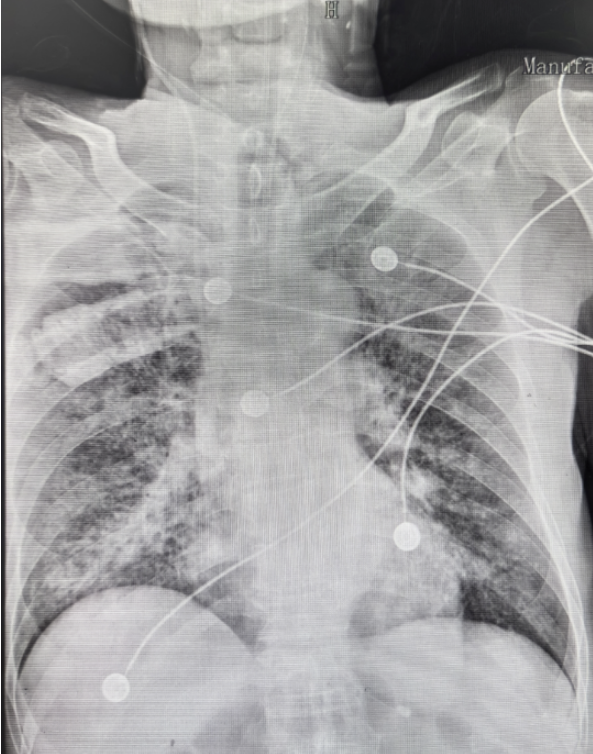

现病史: 患者12月26日被家人发现无诱因出现呼吸困难、全身湿冷, 伴咳嗽咳痰, 黄黏痰。测体温不高, 遂就诊于我院急诊科。床旁胸片示双肺多发片状阴影(图1)。血气分析示Ⅰ型呼吸衰竭, 测血压80/45mmHg; 立即予无创通气、多巴胺持续泵入、抗感染等治疗后收入我科。

图1 患者急诊+胸部X线片